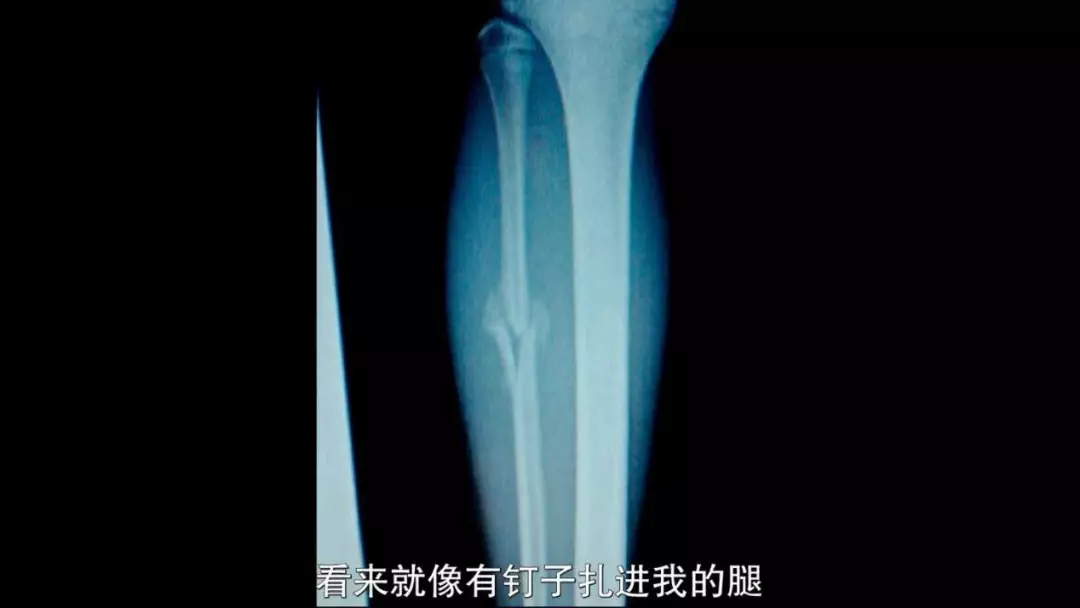

一名受害者,彼时因为训练成绩下降,受到了教练的「重点关注」,加大了训练量。

尽管她自己感到腿部的伤病十分严重,每次跳跃都钻心得疼,但纳萨尔却一直告诉她:

「没事,你的腿没有任何问题,去训练吧。」

终于有一天,她躺在地上,再也无力站起来。

她一瘸一拐地走出训练基地,走进医院,正经地做了检查:

腿部粉碎性骨折。

体操世界,几乎再也与她无缘。